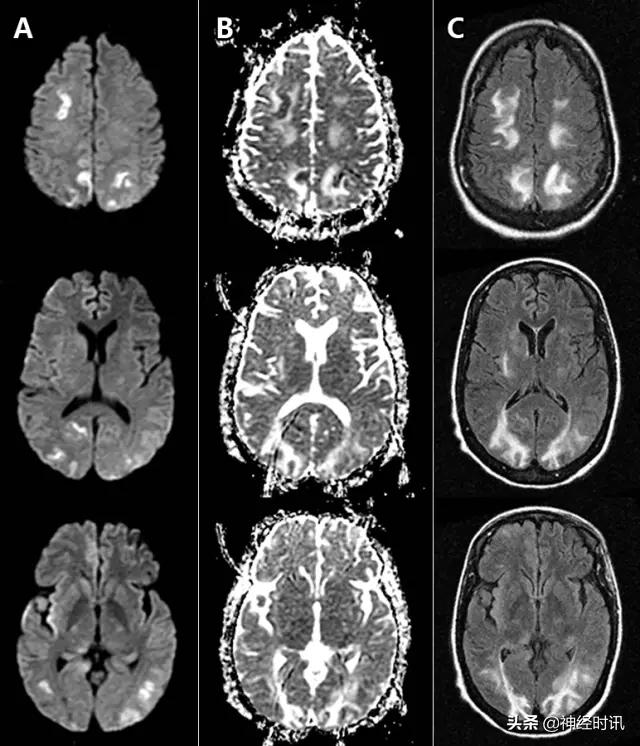

缺血缺氧性脑病

缺血缺氧性脑病(HIE)是全脑缺氧的结果。最常见的原因是心脏骤停、呼吸衰竭和休克。严重的患者大脑皮质和深部灰质均受累(图7)。较轻的患者可以见到边缘带梗死类型。罕有纯白质型,这可能是全脑缺血诱发脱髓鞘表现。小脑通常不受累。

图7 一例31岁男性,有*洛因海**和*卡因可**滥用史,出现无脉性电活动心搏骤停。MRI显示双侧顶枕叶和额叶、双侧丘脑弥漫性弥散受限(A:DWI,B:ADC)、T2-FLAIR高信号(C:FLAIR),符合全脑缺氧性损伤。